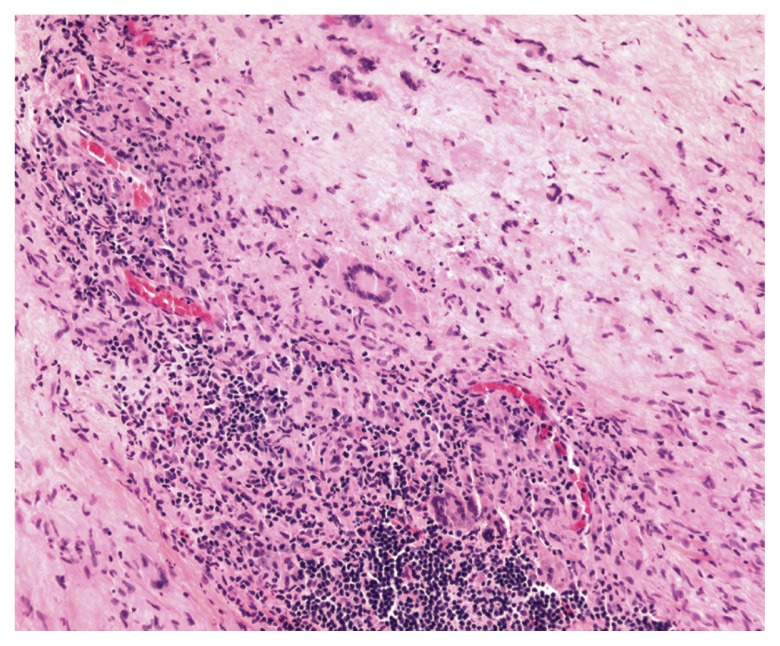

Figure 3.

Hematoxylin and eosin stain of conjunctival biopsy demonstrating giant cells predominantly of the Touton type with leukemic cell infiltration of tissues.